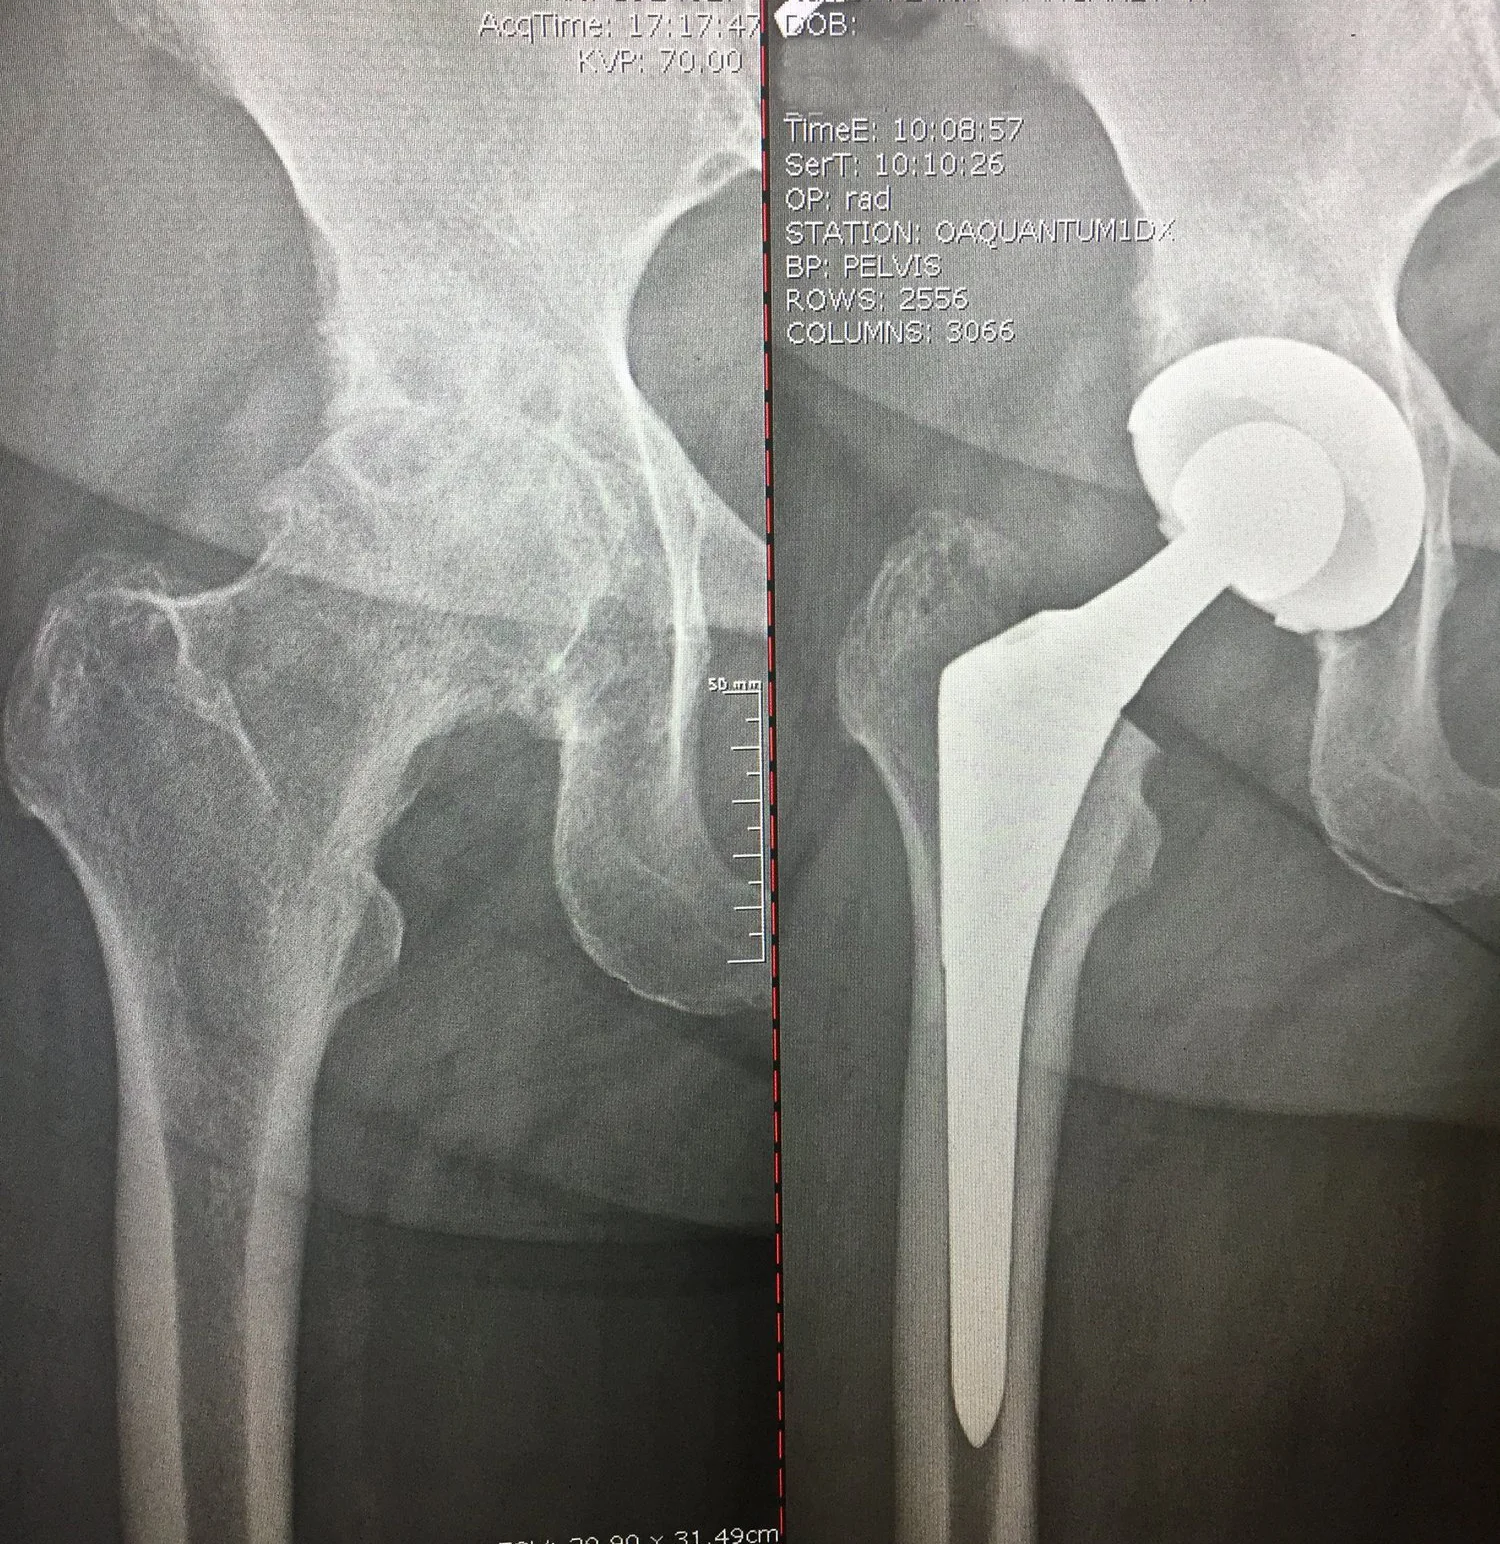

Before: Previous osteotomy surgery with screw fixation for dysplasia - now very arthritic and bone on bone

After: Total Hip Replacement

OMNI

Before: Bone on bone arthritis

After: Total Hip Replacement on 95 y/o male

BIOMET